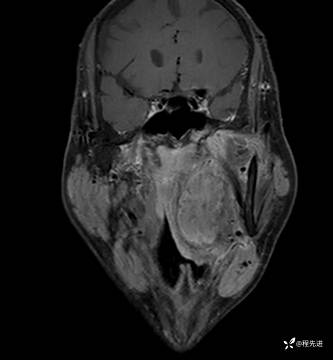

MRI平扫+增强:

T2压脂:

T1:

T1增强: